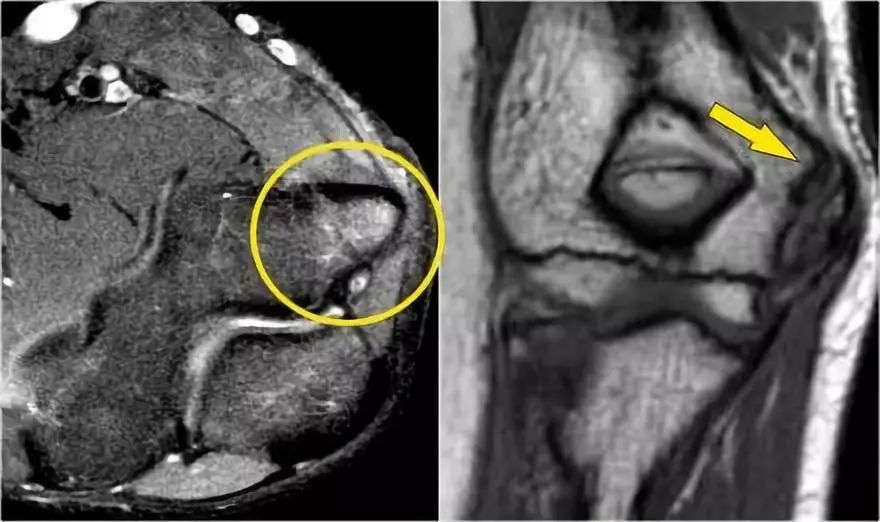

在下图可以看到,在左上方T1W图像中,伸肌中存在高信号脂肪,肌肉体积减少,这表明脂肪萎缩。右上方的轴向图像显示了旋后肌中更近端的质量。

矢状图像证实这是脂肪瘤。因此萎缩是骨间后神经受压的结果,骨间后神经是桡神经的一个分支。